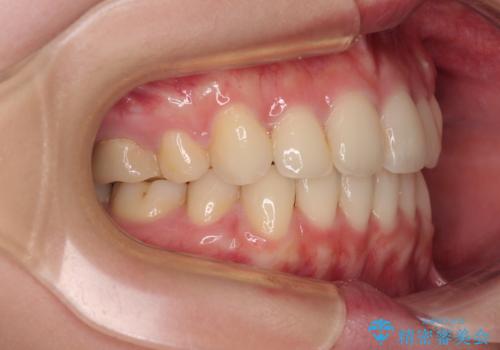

前歯のデコボコを抜歯矯正でスッキリした口元に

- 八重歯やクロスバイトを気にして来院された患者様です。

口元の突出感はありませんでしたが、デコボコが強く、非抜歯矯正とすると出っ歯仕上がりとなる可能性があったため、上下左右の第一小臼歯4本を抜歯し、ワイヤー装置にて矯正治療を行うこととしました。

デコボコがスッキリするだけでなく、口元の突出感も少し改善され、満足のいく仕上がりとなりました。